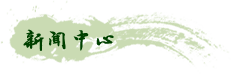

入院时症见:咳嗽,呈阵发性,晨起时明显,咯白色粘痰,量多不易咯,伴痰中带血,色暗红,具体量叙述不清,每日出现1~3次,伴喘促,以急走及爬楼后明显,休息后可缓解,时感全身乏力。入院后患者仍反复出现痰中带血的情况,入院胸部CT提示:双肺纹理增多、紊乱,肺叶透亮度增高;右肺中叶见少许纤维条索影,余肺内未见明显渗出及实质性病变;纵隔内未见肿大淋巴结;双侧胸腔未见积液。心外形不大,大血管壁钙化。右侧第8前肋陈旧性骨折。根据患者CT提示以及患者自身情况,在上海中医药大学附属岳阳中西医结合医院张恩丝老师的指导下,为进一步明确诊断以及查找咯血的原因,为爷爷完善了支气管镜检查。